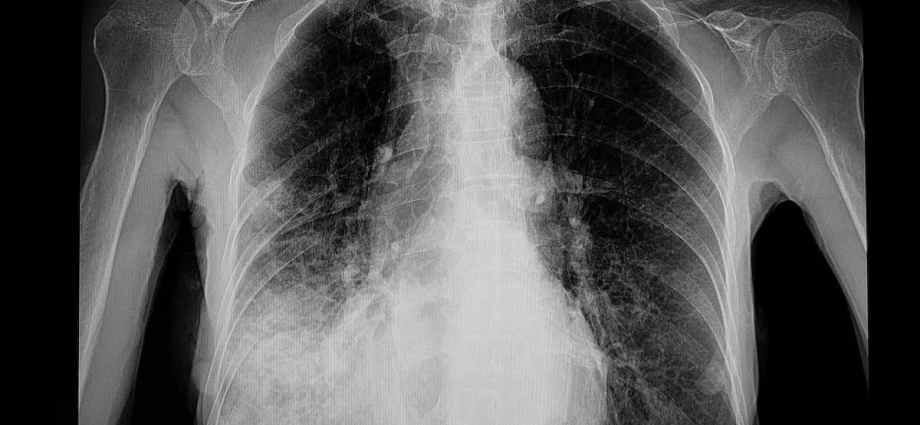

But there are two other types: Septicemic plague, which spreads throughout the body, and pneumonic plague, which infects the lungs.

Pneumonic plague, which caused the Arizona death, is also the easiest to spread, AP said.